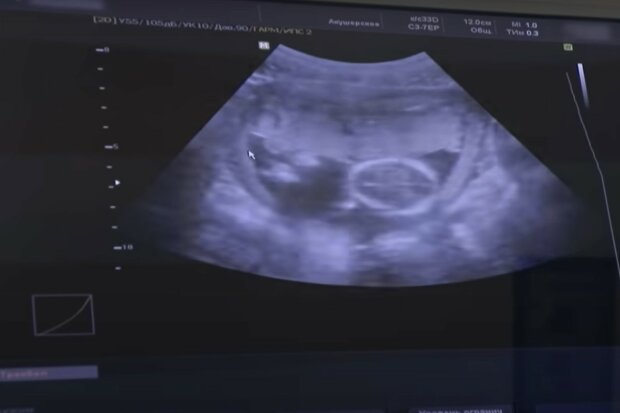

Przesuwałem głowicą po brzuchu dziewczyny. Ona patrzyła na ekran, a jej matka demonstracyjnie odwróciła się, ale zerkała przez ramię.

„Zdrowe dziecko, duże, około 18 tygodni... Och, widzę, kto to jest, chcecie wiedzieć?”

„Możecie powiedzieć?” – matka dziewczyny ożywiła się, odwróciła i wpatrzyła w monitor. Jednak nie było jej to obojętne.

„Macie dziewczynkę.”

„Och, doktorze!” – matka dziewczyny zmieniła się nie do poznania. – „To takie szczęście, dziewczynka... Dziękuję, doktorze! Kasia, wybacz mi, chyba przesadziłam... Będę miała wnuczkę. Ależ to wspaniale. Doktorze, wyobrażacie sobie?”

„Oczywiście” – uśmiechnąłem się. Kobieta rozpromieniła się. Uśmiechnęła się, chwyciła córkę za rękę i nawet się rozpłakała. Dziwne, jak ludzie zmieniają się pod wpływem zwykłego obrazu na ekranie.